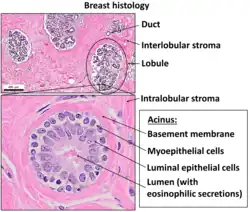

Myoepithelial cells (sometimes referred to as myoepithelium) are cells usually found in glandular epithelium as a thin layer above the basement membrane but generally beneath the luminal cells. These may be positive for alpha smooth muscle actin and can contract and expel the secretions of exocrine glands. They are found in the sweat glands, mammary glands, lacrimal glands, and salivary glands. Myoepithelial cells in these cases constitute the basal cell layer of an epithelium that harbors the epithelial progenitor. In the case of wound healing, myoepithelial cells reactively proliferate. Presence of myoepithelial cells in a hyperplastic tissue proves the benignity of the gland and, when absent, indicates cancer. Only rare cancers like adenoid cystic carcinomas contains myoepithelial cells as one of the malignant components.

Myoepithelial cells are true epithelial cells positive for keratins, not to be confused with myofibroblasts which are true mesenchymal cells positive for vimentin. These cells are generally positive for alpha smooth muscle actin (αSMA), cytokeratin 5/6 and other high molecular weight cytokeratins, p63 and caldesmon. Myoepithelial cells are stellate in shape and are also known as basket cells. They lie between the basement membrane and glandular epithelium. Each cell consists of a cell body from which 4-8 processes radiate and embrace the secretory unit. Myoepithelial cells have contractile functions. They help in expelling secretions from the lumen of secretory units and facilitate the movement of saliva in salivary ducts.